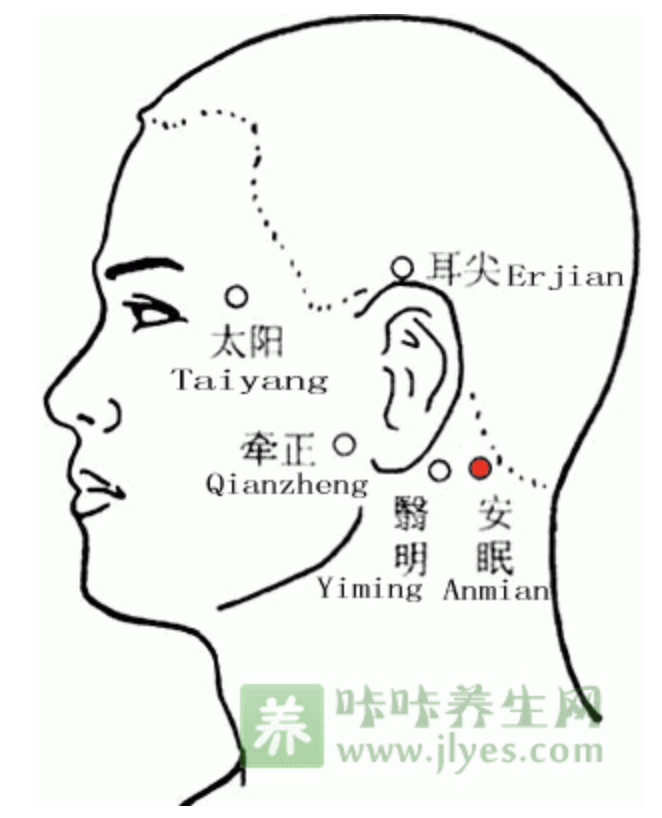

太阳

【定位】 在颞(niè)部,当眉梢与目外眦之间,向后约 1 横指的凹陷处(图 10-35)。

【主治】 偏正头痛,目赤肿痛,目眩,目涩,牙痛,三叉神经痛。

【刺灸法】 直刺或斜刺 0.3 ~ 0.5 寸;或用三棱针点刺出血。禁灸。

安眠

【定位】 在项部,当翳风穴与风池穴连线的中点。

【主治】 失眠,头痛,眩晕,癫狂。

【刺灸法】 直刺 0.8 ~ 1.2 寸;可灸。